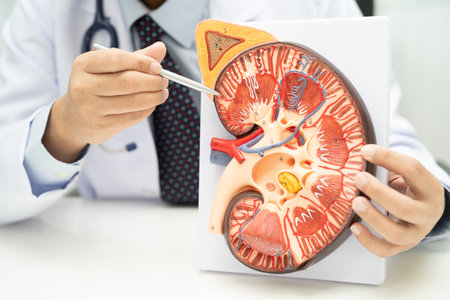

Kidney disease, Chronic kidney disease ckd, Doctor hold human model to treat and study in hospital.

Chronic kidney disease, doctor with model for treatment urinary system, urology, Estimated glomerular filtration rate eGFR.

Chronic kidney disease, doctor with model for treatment urinary system, urology, Estimated glomerular filtration rate eGFR.

Detailed model of a human kidney held in a hand for educational purposes in a neutral setting

Kidney disease, Chronic kidney disease ckd, Doctor hold human model to treat and study in hospital.

Model of human kidney held in a hand showcasing internal structure and details for educational purposes

Model of human kidney held by hand with colored features visible

Human Kidney Model with Chronic Kidney Disease Damage Held by Doctor